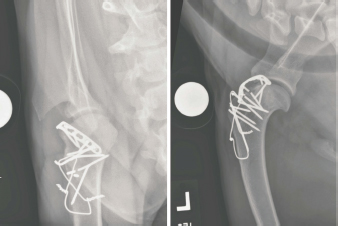

Open surgical reduction and stabilization (Vaughn, 1967; DeAngelis and Schwartz, 1970) was recommended. The dog was premedicated using dexdomitor 300 mcg IV and butorphanol 0.1 mg/kg IV, perioperative cefazolin was given at 30 mg/kg IV and continued Q 8 hours for 24 hours. Anesthesia was induced with 7.6 mg/kg Propofol given over 60–90 seconds to allow intubation, where anesthesia was maintained with Isoflurane. The left thoracic limb was clipped and prepared for aseptic surgery. The dog was positioned in dorsal recumbency and a craniolateral approach to the left scapulohumeral joint was done. During the initial stages of the procedure, the humeral head intermittently luxated cranially, predominately when the scapulohumeral joint was flexed. The acromial head of the deltoid and the sternocephalicus muscles were retracted and the infraspinatus, superficial pectoral, and deep pectoral muscles were incised and reflected to expose the joint capsule. The cranial joint capsule was circumferentially incised to expose the tendon of origin of the biceps brachii muscle and the transverse humeral ligament was incised. An osteotomy of the greater tubercle of the humerus was performed with an oscillating saw, allowing proximal reflection of the supraspinatus muscle. A pneumatic drill and burr were used to create a trapezoidal proximal-to-distal trough centrally in the exposed cancellous bone in the base of the osteotomy site. The trough was sculpted to conform to the dimensions of the bicipital tendon including the proximal myotendinous portion of the biceps brachii muscle (Fig. 2). The biceps brachii tendon was levered laterally into the trough using a Freer periosteal elevator and the humerus no longer luxated when the bicipital tendon was positioned in the trough (Fig. 3). The joint capsule was reopposed using 2-0 PDS placed in an interrupted cruciate pattern which prevented displacement of the tendon. To augment the stability afforded by the capsulorrhaphy, a six-hole 2.0 mm locking compression plate (DePuy Synthes, West Chester, PA) was placed along the craniolateral margin of the distal scapulohumeral joint line. The plate bridged the bicipital tendon and was secured to the humerus with three locking and one cortical 2.0 mm screws (Fig. 4). The greater tubercle was then repositioned on the incised surface of the humerus, 1 cm distal to the tubercle’s original location. The tubercle was secured with two 1.6-mm Kirschner wires and two strands of 18-gauge orthopedic wires placed in a figure-of-eight configuration as a tension band. Five additional 1.6-mm Kirschner wires were placed to further secure the tuberosity to the proximal humerus (Fig. 5). The remainder of the wound was closed in a routine fashion. After obtaining post-operative radiographs (Fig. 6), the left thoracic limb was placed in a Spica splint (DeCamp et al., 2016). Postoperatively, the dog was administered methadone (0.1 mg/kg IV Q 4 hours for two doses), transitioned to tramadol (3.3 mg/kg PO Q 8, beginning the morning following surgery), carprofen (16 mg/kg PO Q 12, beginning in the morning following the surgery), trazodone (3.3 mg/kg PO Q 8, beginning in the evening following the surgery), cefazolin continued (30 mg/kg IV Q 8 for 24 hours), transitioned to cephalexin (33 mg/kg PO Q 12, beginning in the evening following the surgery) and continued through discharge for 14 days.

Fig. 6. Caudocranial (left) and mediolateral (right) projection radiographs of the left scapulohumeral joint obtained immediately following the surgery. The scapulohumeral joint was congruent. A contoured locking compression plate was secured to the craniolateral articular margin of the proximal humerus. The plate was placed following joint capsule closure and bridged the transposed biceps brachii tendon. The greater tubercle was attached, but transposed 1 cm distally, and secured using multiple Kirschner wires and a figure-of-eight tension band wire.

Fig. 7. Caudocranial (left) and mediolateral (right) projections of the left scapulohumeral joint made 14 months following the surgery. The scapulohumeral joint is congruent. Three bone screws engaging the contoured bone plate are fractured, and there is sclerosis of the femoral head and neck. The humeral cortex at the level of the third most distal screw is decreased in mineral opacity and ill-defined.